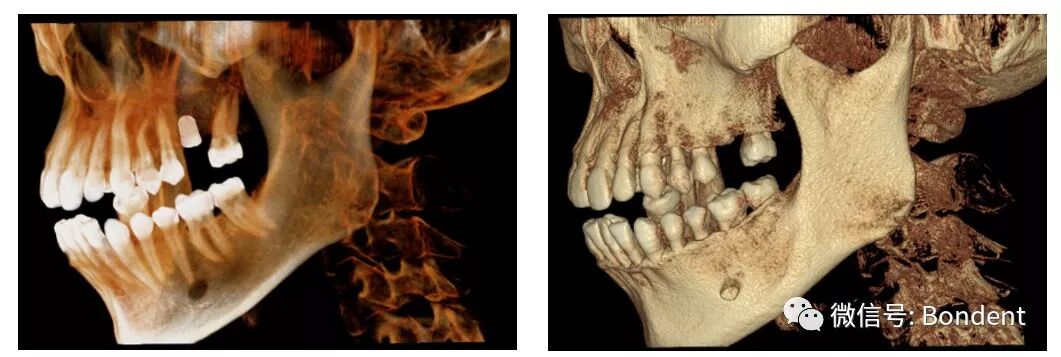

清晰的3D影像為實(shí)現(xiàn)數(shù)字化精準(zhǔn)治療保駕護(hù)航

智能3D全景幫助醫(yī)生便捷直觀地發(fā)現(xiàn)多種牙齒隱患問(wèn)題,醫(yī)患溝通超乎您想像的簡(jiǎn)單,且有效。

OnDemand 3D后處理軟件直接模擬真實(shí)種植場(chǎng)景,更有骨密度精確測(cè)量,醫(yī)患溝通更直觀,手術(shù)更安全,患者更信任。

“伯爵Bondream”智能3D全景由外向內(nèi)33張全景片觀查

普通全景圖(同一患者前牙區(qū)埋伏牙觀察)